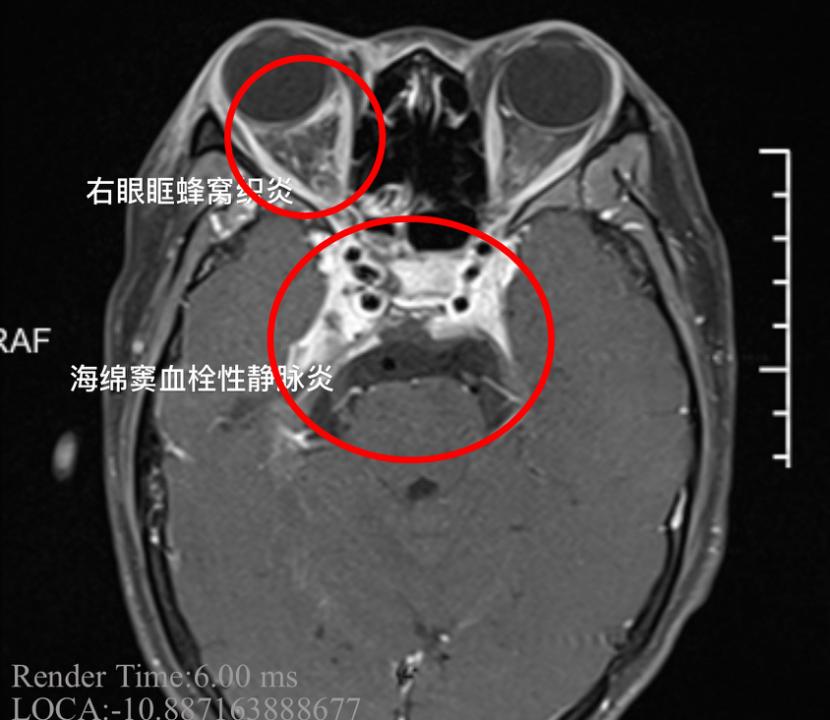

小杨患上了“海绵窦血栓性静脉炎”

这是一种严重的颅内感染

“女孩的右眼外凸,眼球已经固定无法转动,瞳孔扩大,对光反射消失,多组颅神经受累,这都是海绵窦严重感染的征象,同时我们发现患者的脑膜刺激征阳性,海绵窦的炎症已经扩散,出现了脑膜炎,继续进展随时有生命危险。”